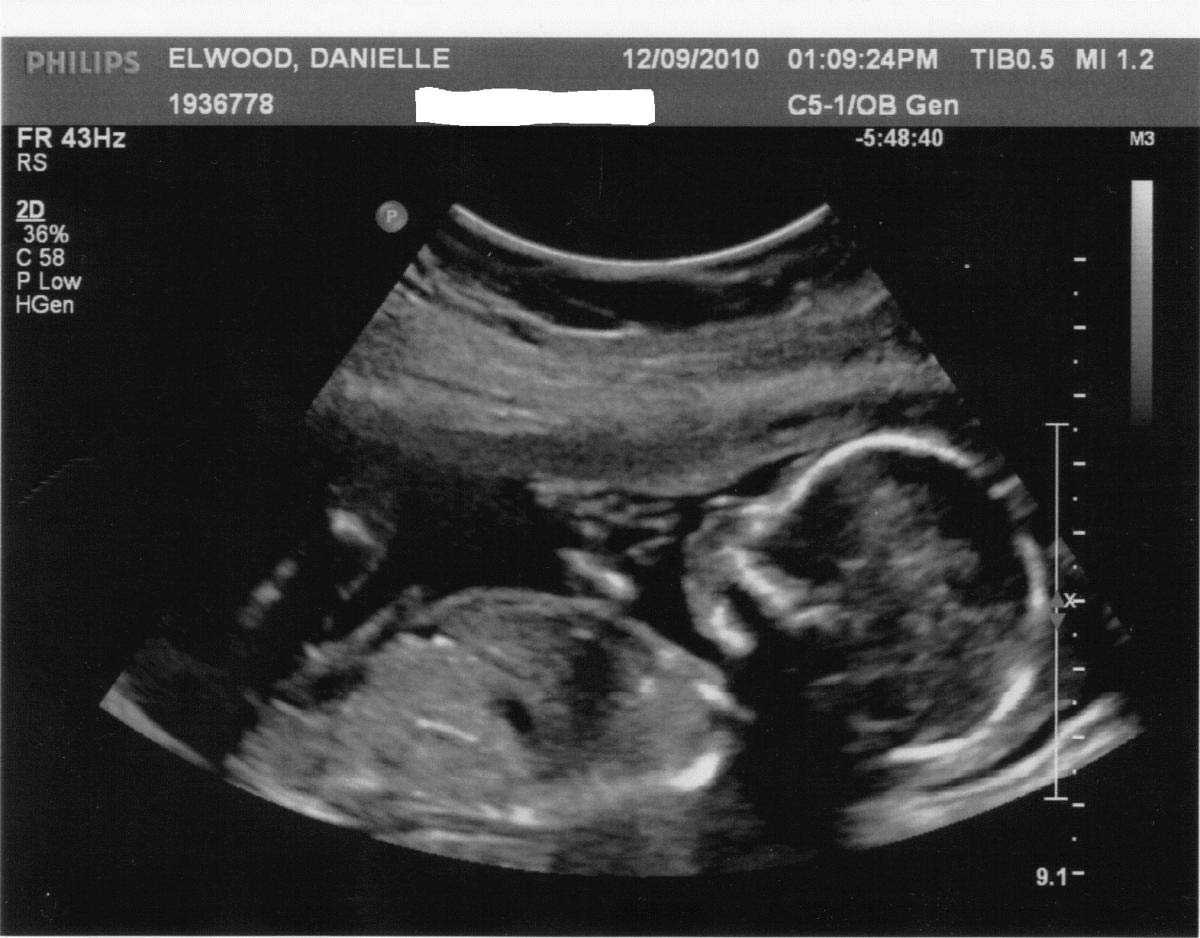

На этом сроке будущую маму могут отправить на третий скрининг. УЗИ плода на 29 неделе беременности от зачатия – обязательная часть обследования.

— Третий скрининг проводится для того, чтобы исключить патологические состояния течения беременности: фетоплацентарную недостаточность; внутриутробное отставание в развитии плода; кислородное голодание малыша (хроническая гипоксия); развитие внутриутробной инфекции; обвитие малыша пуповиной, преждевременное старение плаценты или ее предлежание, многоводие и маловодие, — объясняет врач акушер-гинеколог Олеся Побединская, pobedinskaya_81.

Чтобы убедиться, что кровоток в матке и плаценте не нарушен, проводится также доплерометрия.

Стоит отметить, что УЗИ на 29 неделе назначают редко, ведь плановое обследование третьего триместра проходят на 30-34 неделе. И все же будущей маме его могут назначить, если недавно она перенесла инфекционное заболевание.

Диагноз низкая плацента – еще одна причина УЗИ на 29 неделе беременности. Если есть подозрение на сокращение шейки матки, это может привести к выкидышу на поздних сроках.

Одной из важнейших задач УЗИ является выяснение предлежания плода. Обычно к этой неделе он занимает правильную позицию, но может до конца держать родителей в напряжении и поменять положение только перед родами.

Проверяют во время исследования и развитие ребенка, его фетометрию: бипариетальный и лобно-затылочный размеры, окружность живота и головы, длину самых крупных костей.

Что касается организма матери, то на УЗИ врач оценивает количество и качество амниотической жидкости как один из показателей нормы развития ребенка. Ее объем может говорить о работе почек малыша, а консистенция – о возможных инфекциях.

УЗИ позволит установить соответствие развития плода сроку вынашивания

Особое внимание врач обращает на внутренние органы ребенка. При описании картины на экране обязательно учитывается степень зрелости плаценты и количество околоплодных вод. Параллельно выслушивается сердцебиение плода

Параллельно выслушивается сердцебиение плода. В норме оно составляет 160-180 ударов на минуту.

При превышении этого значения врач может заподозрить кислородное голодание малыша. В таком случае дополнительно проводится доплеровское исследование пуповинного кровотока.

На данном этапе УЗИ исключит замершую беременность и покажет размеры матки, будет точно определен пол ребенка. Будущая мама сможет увидеть все органы малыша и получить снимок плода. Предлагаем вам посмотреть видео УЗИ плода на 29 неделе беременности, а также рассмотреть фото малыша выше.